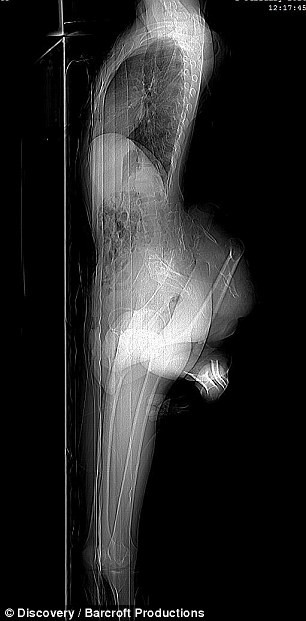

Arun Kumar năm nay 22 tuổi hiện sống tại Uttar Pradesh (Ấn Độ) bẩm sinh đã có 2 chân thừa ở phần lưng dưới phía sau, trong đó có một chân phát triển chưa đầy đủ, còn một chân thì vĩnh viễn lòng thòng ở đầu gối.

Mặc dù không thể cử động hai chân thừa nhưng người bốn chân này cho biết hai chân thừa này vẫn có cảm giác. Ngoài ra hai chân này cũng khiến phần lưng phải chịu thêm một gánh nặng, ảnh hưởng đến dáng người và chuyện đi lại của thanh niên này.

Dù đã hỏi qua nhiều bệnh viện nhưng các bác sĩ cho rằng phẫu thuật cắt chân thừa rất nguy hiểm vì Arun còn nhỏ. Nhưng giờ đây đã trưởng thành thì lời khẩn cầu của Arun có thể sẽ được đáp ứng khi bác sĩ phẫu thuật chỉnh hình Hermant Sharma đã kiểm tra và phát hiện ra thanh niên này có 2 khung chậu.

Vì vậy nên cần tiến hành một loạt các xét nghiệm tiếp theo xem Arun có thể có thận thừa, ống tiểu thừa hay bàng quang thừa hay không rồi mới xác định khả năng phẫu thuật